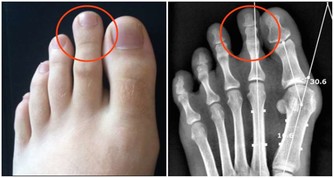

******3、 手腳冰涼*****

手腳冰涼是一種常見的現象,但是在室溫正常又沒有其它狀況的情況下,突然性的手腳冰涼就需要警惕了!這種情況很可能就是心臟出現問題的徵兆。心臟出現問題後,心肌供血出現障礙,血液循環不順暢,由此會引起突然手腳冰涼甚至抽筋的情況。